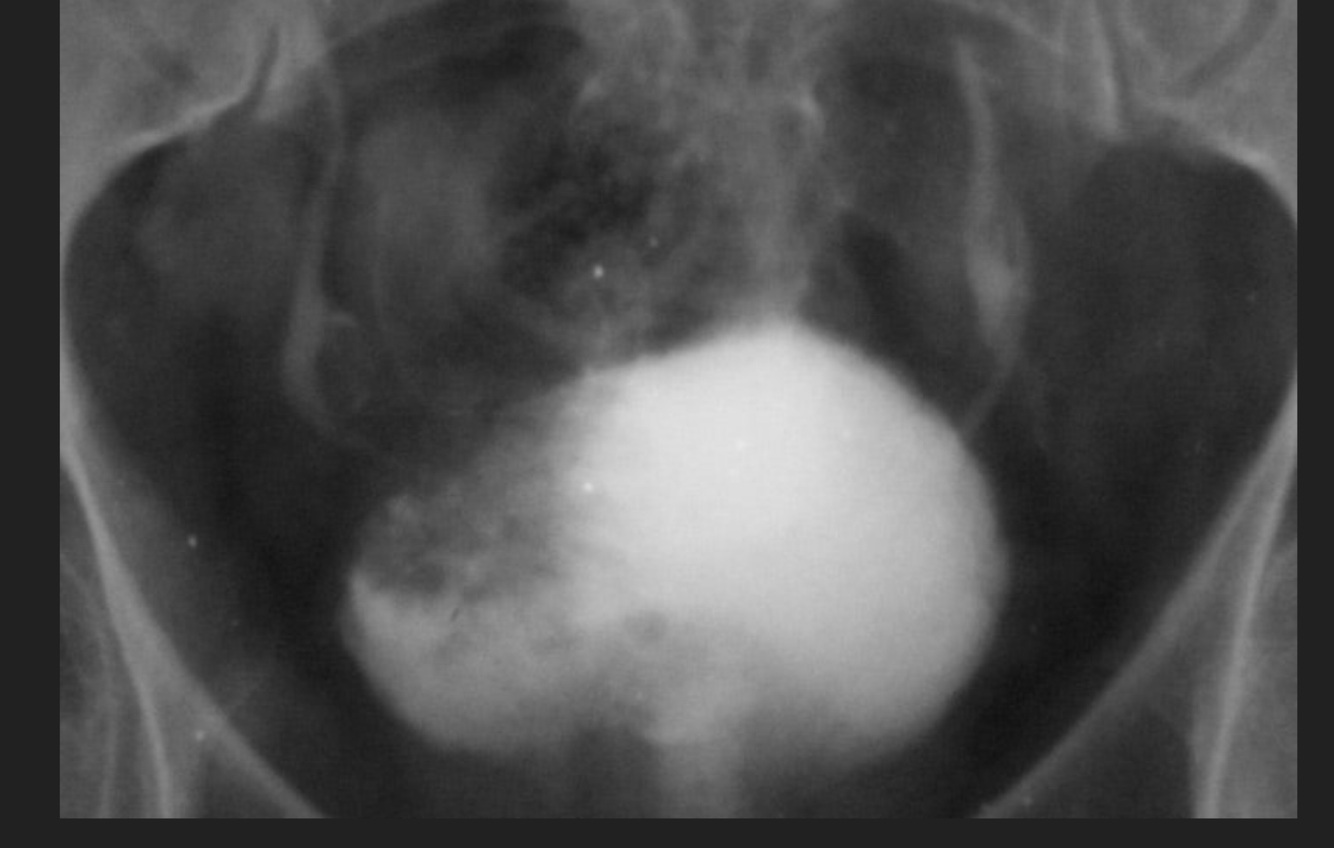

4

Q

UE Nefromegalia secundaria a:

A

Hidronefrosis